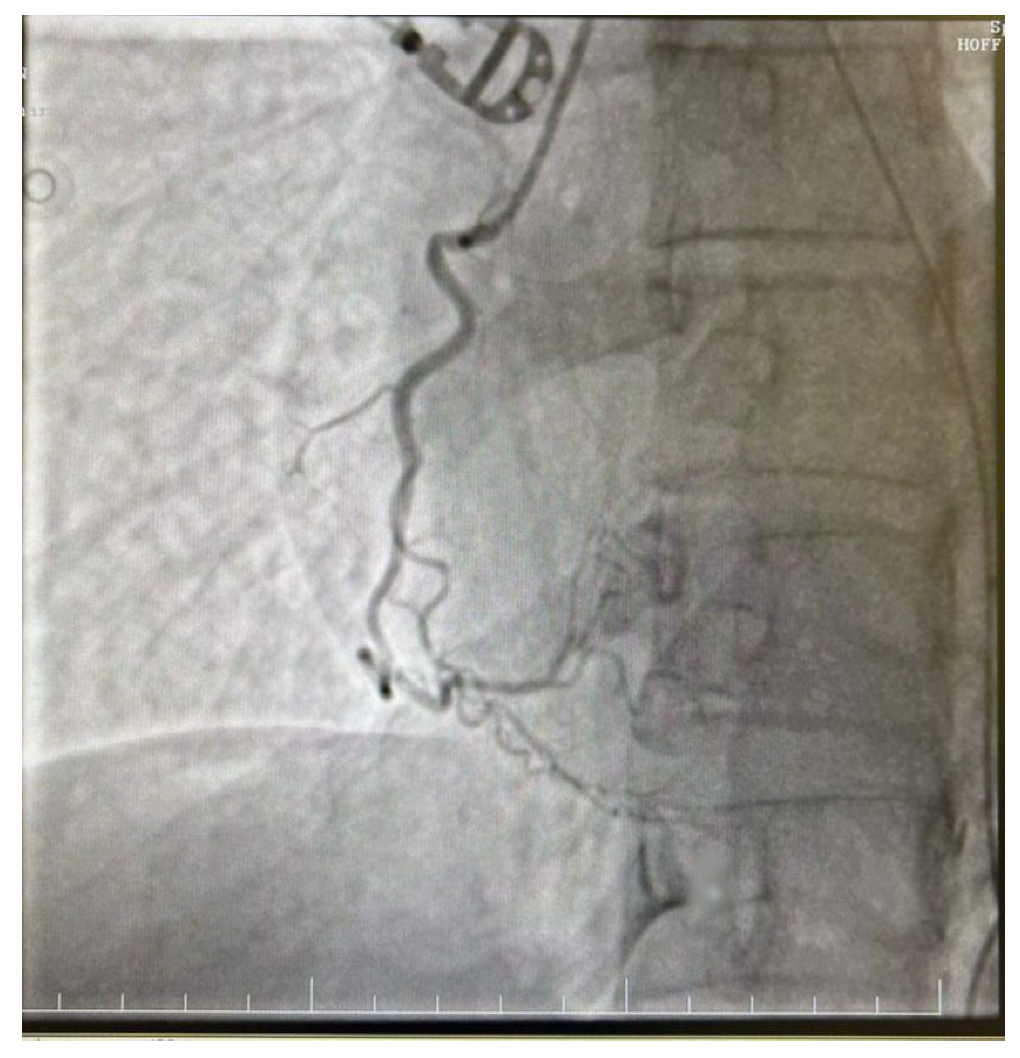

The decision was made to perform a coronarography, which showed no signs of acute or chronic coronary obstruction (Figure 5 and Figure 6). The patient was put on a continuous infusion of 0.01 micrograms/kg/min of noradrenaline and 1.8 mcg/kg/min of dobutamine with 40 mg of enoxaparin given the next day. She remained intubated for 48 h and the improvement of her hemodynamic status allowed the discontinuation of the inotropic medication the following day. After the steady improvement of the respiratory and cardiac functions, the patient’s clinical status allowed extubation with spontaneous breathing. The patient was started on the standard therapy for cardiac insufficiency, consisting of beta blockers, antiarrhythmic therapy, Angiotensin-converting enzyme (ACE) inhibitors and levosimendan. The following echocardiogram showed slow but steady improvement in the cardiac function. She was discharged from intensive care on day 6 and from the hospital on day 10. The echocardiogram conducted on the day she was discharged from the ICU revealed an EF of 25%, with akinesia of the ventricular apex and medio/apical segments, with no right ventricular dilatation and mild mitral regurgitation. On day 9 after HIPEC, the echocardiogram revealed an EF of 30–35% with hypokinesis of the apex and middle-to-apical segments of the heart. The patient did not complain of angina or dyspnea and tolerated lying in the supine position. She was discharged from the hospital on a combination of beta blockers, antiarrhythmic medication and ACE inhibitors, with a follow-up echocardiogram after one month.

Figure 5.

Right dominant coronary system without significant angiographic lesions.